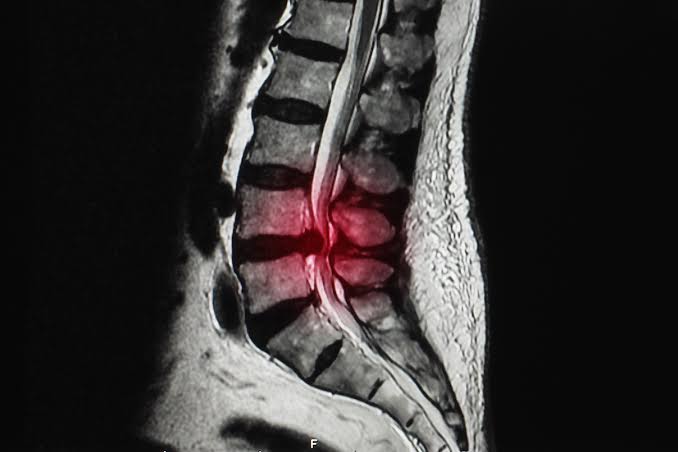

Besides physical therapy. Are there any other body part workout routines I can do? Please help. I miss working out!!

I have an L4/L5 hernia, this stretching routine pretty much fixes all problems for me.

Depends, I've had one for 3 1/2 years. The worst thing you can do is nothing, believe me.

I took a break from any leg and lower back training for 7 months last year, since then, I've had my back go out in my sleep out of the blue three times in 10 months. This is not something I've experienced before.